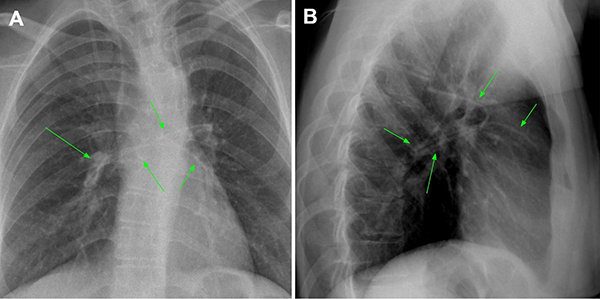

Tras 2 meses, la paciente volvió a consultar en guardia por náuseas, cefalea bifrontal con irradiación holocraneana de intensidad moderada y vómitos. Al examen físico se constató limitación de la mirada superior y colección líquida sobre herida craneal de derivación. Se realizó TC de cerebro con evidencia de ventriculomegalia y desconexión de catéter distal a la válvula (Figura 1). El estudio radiográfico reveló migración caudal del segmento distal del catéter al corazón (Figura 2). El segmento migrado fue rescatado mediante un abordaje endovascular transfemoral, en el cual se enroscó el catéter migrado con un catéter pigtail y se lo desplazó hasta la vena ilíaca primitiva izquierda para luego ser capturado a nivel ilíaco con un lazo trilobulado (Figura 3).

Figura 2. A y B. Radiografías de frente y perfil respectivamente realizadas previo a la intervención endovascular en donde se evidencia migración del catéter distal a la cavidad cardíaca (flechas verdes).